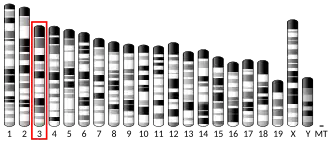

Neprilysin (/ˌnɛprɪˈlaɪsɪn/; also known as membrane metallo-endopeptidase (MME), neutral endopeptidase (NEP), cluster of differentiation 10 (CD10) and common acute lymphoblastic leukemia antigen (CALLA)) is an enzyme that in humans is encoded by the MME gene. Neprilysin is a zinc-dependent metalloprotease that cleaves peptides at the amino side of hydrophobic residues and inactivates several peptide hormones including glucagon, enkephalins, substance P, neurotensin, oxytocin, and bradykinin.[5] It also degrades the amyloid beta peptide whose abnormal folding and aggregation in neural tissue has been implicated as a cause of Alzheimer's disease. Synthesized as a membrane-bound protein, the neprilysin ectodomain is released into the extracellular domain after it has been transported from the Golgi apparatus to the cell surface.

Neprilysin is expressed in a wide variety of tissues and is particularly abundant in kidney. It is also a common acute lymphocytic leukemia antigen that is an important cell surface marker in the diagnosis of human acute lymphocytic leukemia (ALL). This protein is present on leukemic cells of pre-B phenotype, which represent 85% of cases of ALL.[5]